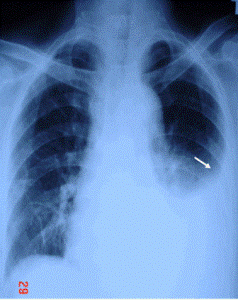

- X-Quang phổi ( giúp xác định tràn dịch màng phổi)